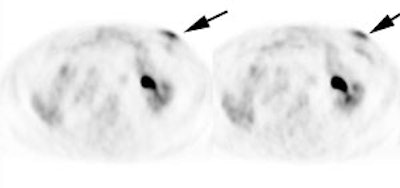

|

Marrow activity: The images below are from two separate patients each showing mild FDG accumulation within the vertebral bodies. |